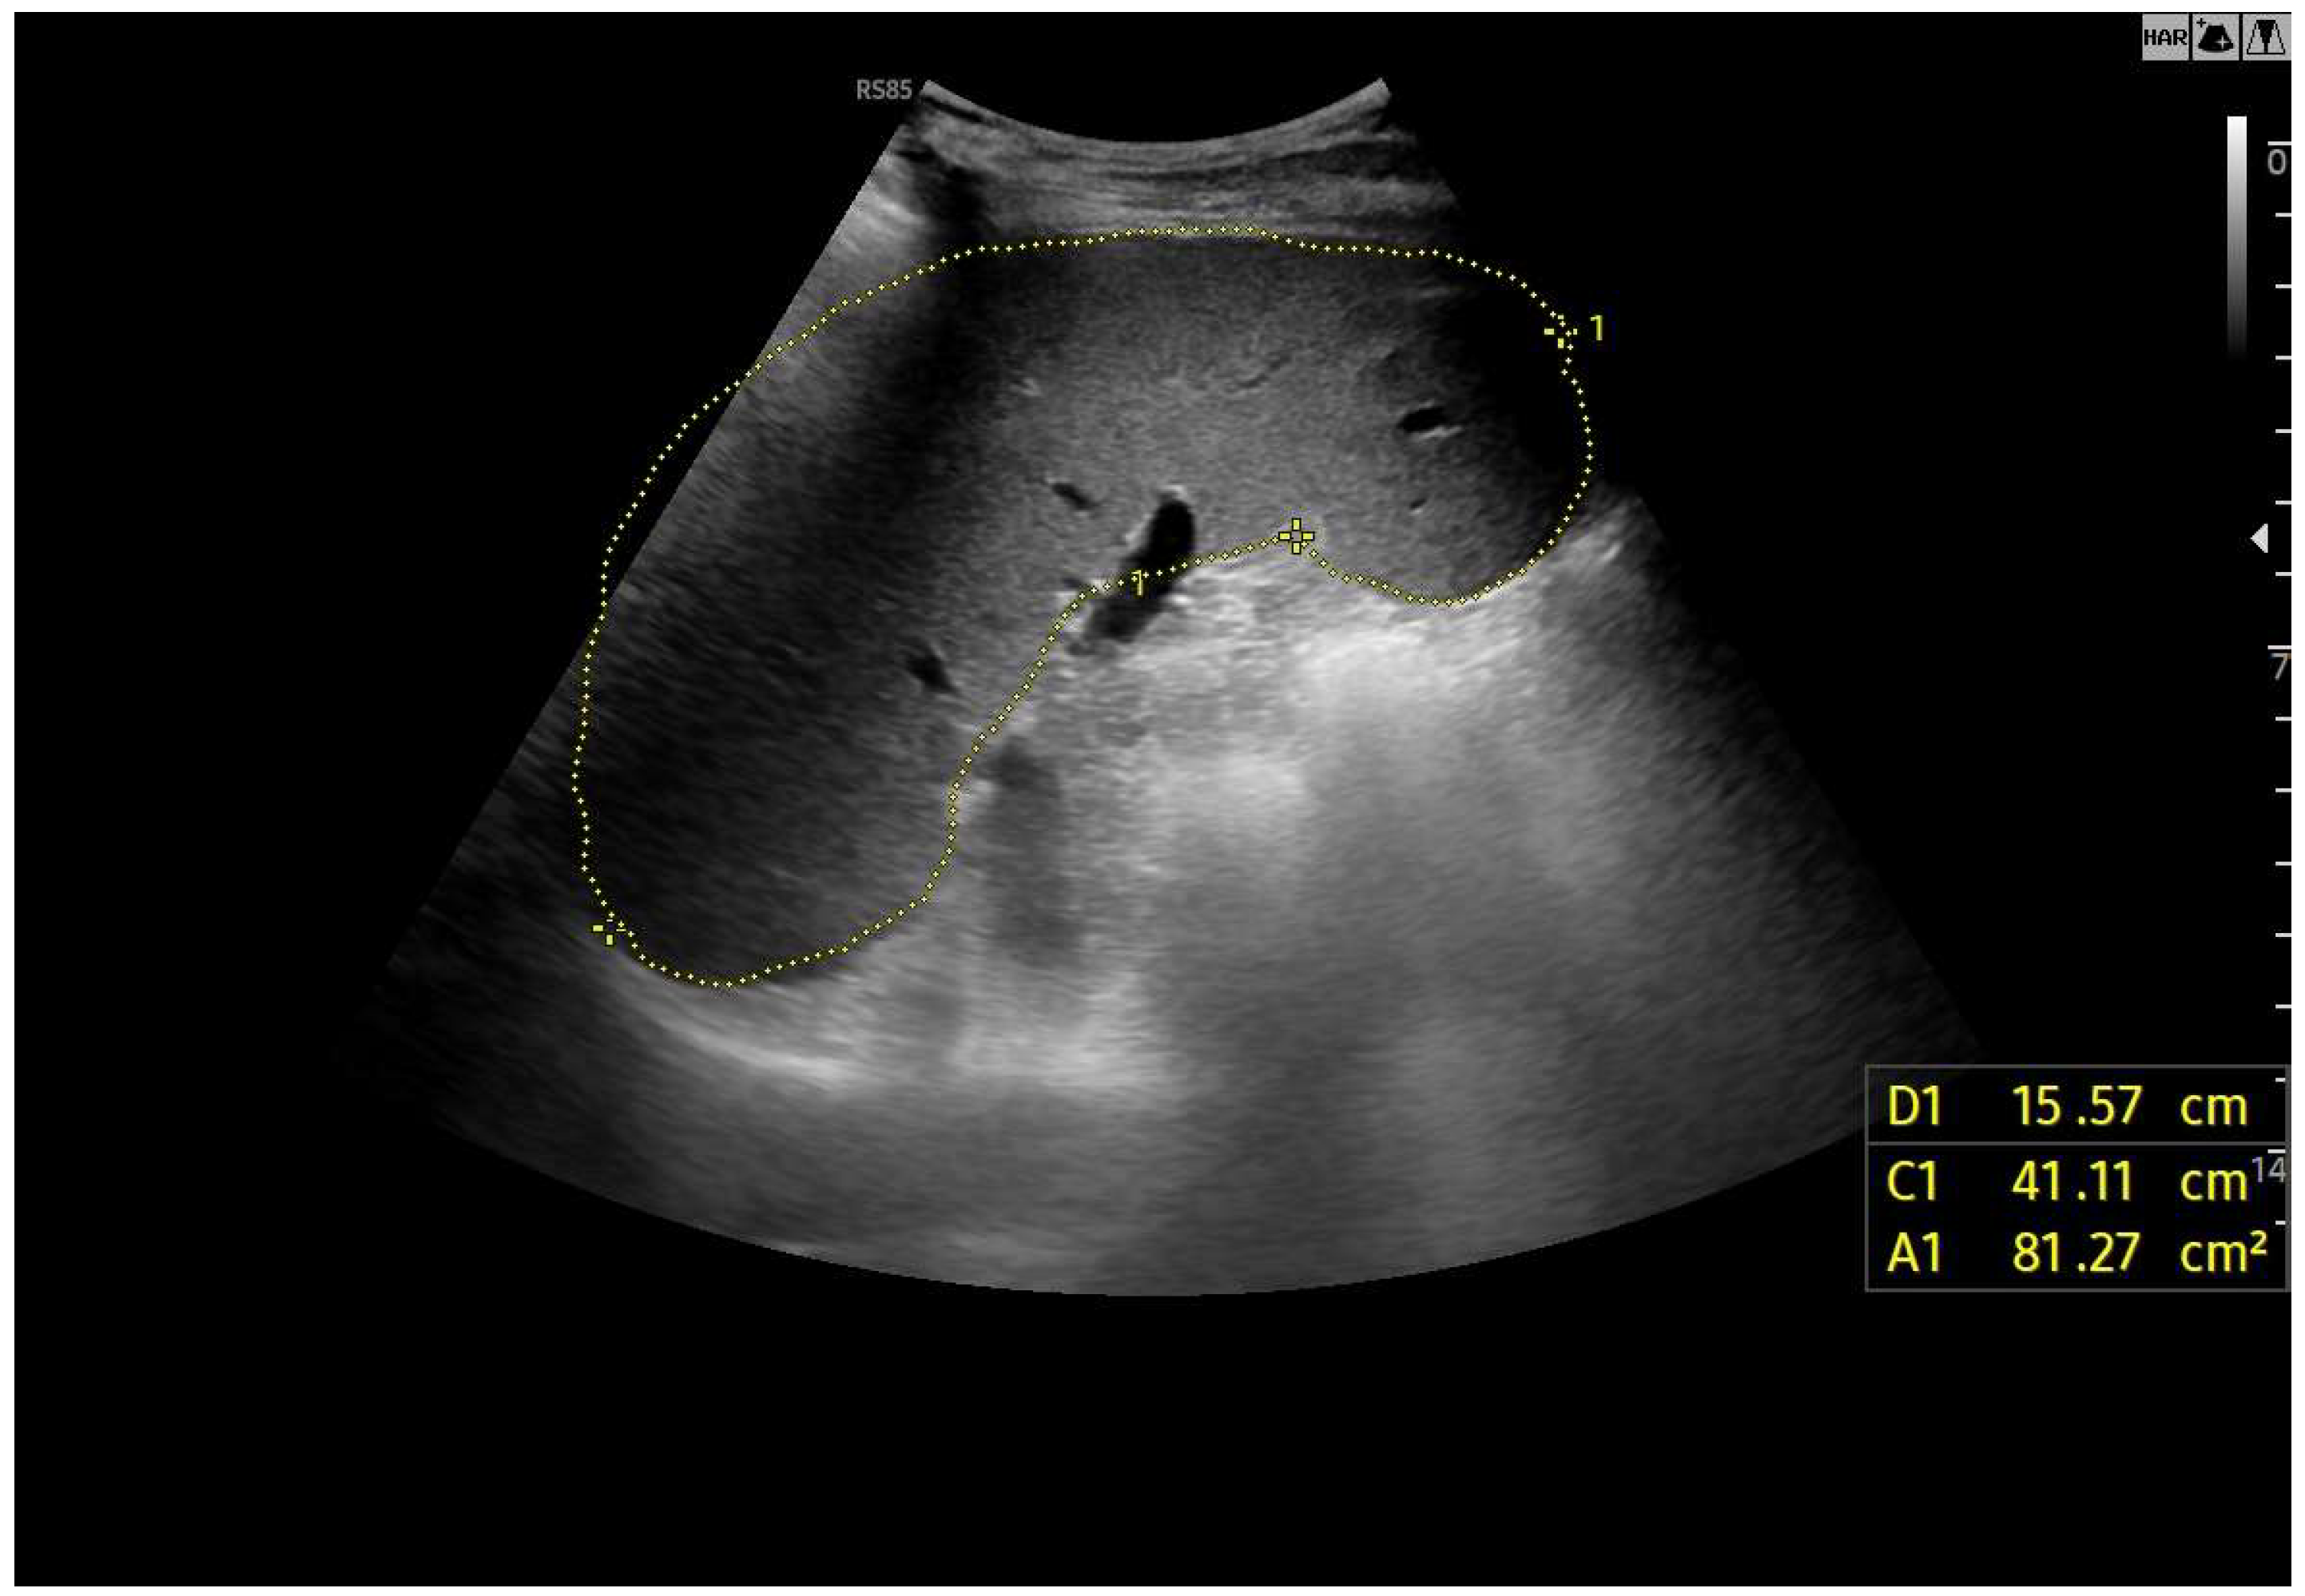

A cohort analysis involving 55 individuals who had undergone the Fontan procedure demonstrated that 67% displayed irregular hepatic echotexture or surface nodularity, changes that showed a temporal association with the duration since surgery. Severe congestion with PHTN may present with dilated portal veins (diameter > 13 mm), enlarged paraumbilical veins, collateral circulation, splenomegaly (Figure 9), ascites, and reversal of portal vein flow [50,52,53].

Figure 9.

Splenomegaly: bipolar diameter 16 cm (normal value: 12 cm); sectional area 81 cm2 (normal value: 45 cm2).